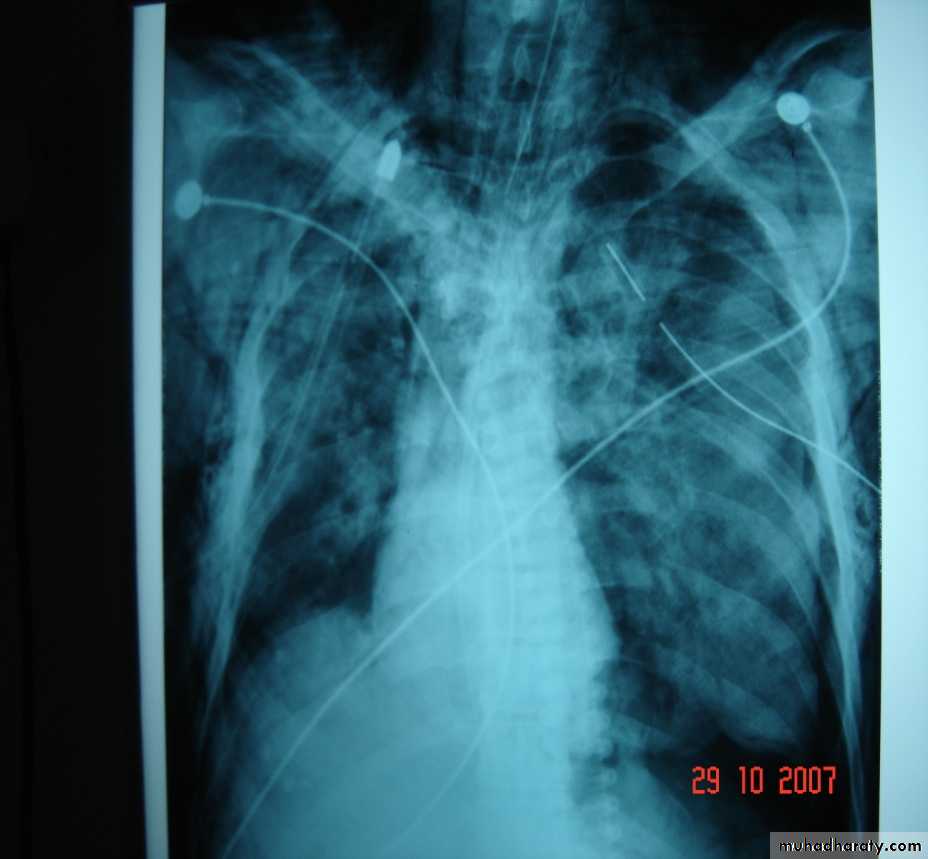

• Complications of chest injuries 1-ARDS: Syndrome of acute RF with the formation of a non –cardiogenic pulmonary edema leading to reduced lung compliance and hypoxaemia which is refractory to oxygen therapy characterized by bilateral diffuse pulmonary infiltrate on chest X-ray (white lung) .A less severe case (ALI=acute lung injury ) which consists of a non specific pathological changes in the lung in response to a specific insult . 2-Atelectasis3-Infection4-Pulmonary embolism5-Air embolism6-Traecheal complications7-Cardiac arrhythmias